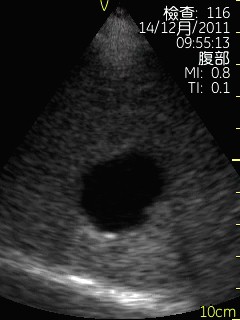

Vscan临床图片 腹部